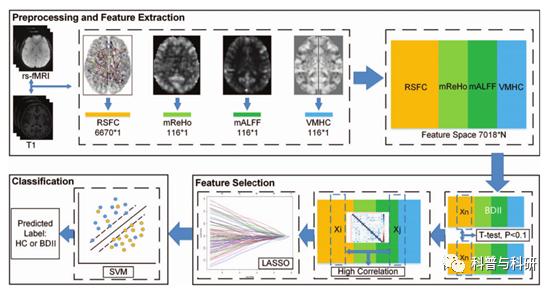

影像学预处理+多指标分析 |

1、影像学数据预处理 2、各个影像学指标的简单介绍(ALFF、fALFF、ReHo、PerAF等简单指标) 3、影像学指标的数据处理 4、功能连接矩阵的提取 |

多指标融合分类诊断 |

1、基于多指标疾病分类/诊断的原理 2、LASSO特征选择 3、MultiKernel SVM分类的基本原理 4、代码解读 5、代码实操练习 |

基于功能连接矩阵的SVM分类 |

1、基于功能连接矩阵的SVM分类基本原理+流程介绍 2、相关高质量文章介绍 3、代码解读 4、代码实操练习 |